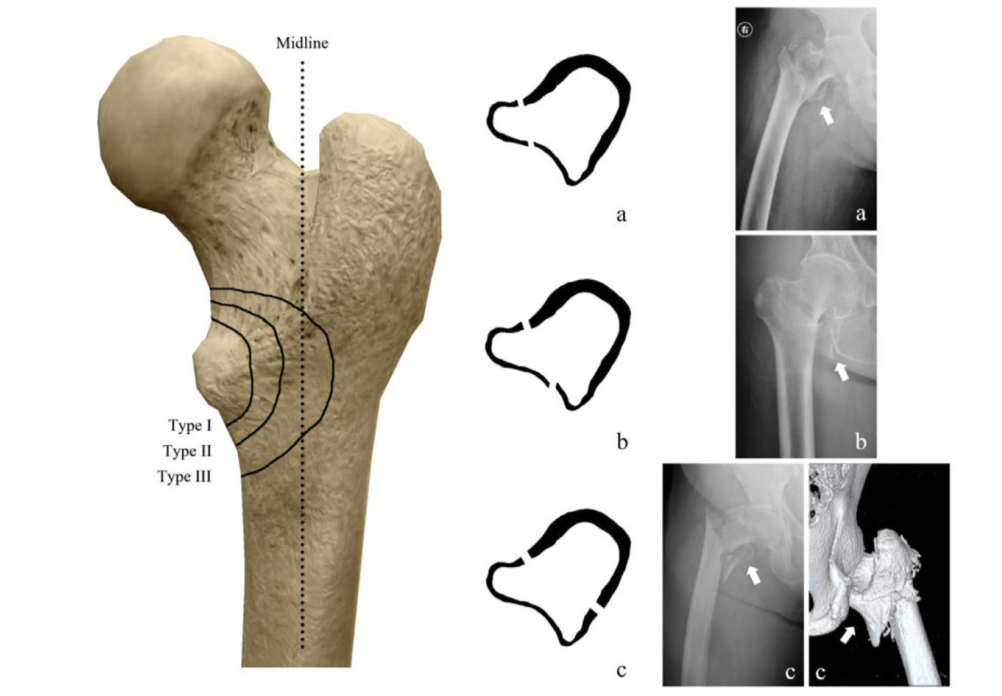

粗隆间骨折好发于老龄患者,为三大骨质疏松性骨折之一,通常需采用内固定治疗。粗隆间骨折内固定的选择,与骨折类型密切相关。关于小转子及内侧壁的重要性,已经越来越受到重视,部分内固定的失效也与其相关。有学者研究了粗隆间骨折累及小转子及内侧壁的大小与内固定失效的关系,结果发表在Injury期刊上。